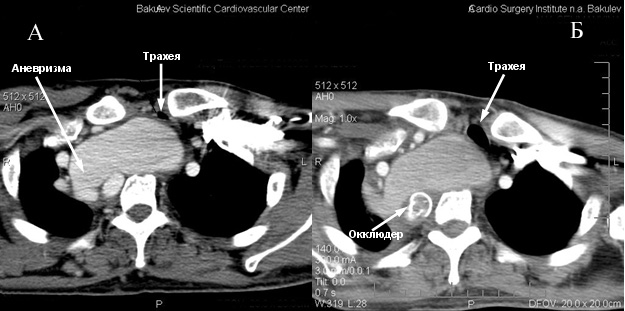

Аневризма позвоночной артерии оттесняет брахиоцефальный ствол и правую плечеголовную вену, суживая ее. Пищевод и трахея также оттеснены вперед и влево, последняя сужена до 6 мм (трахея сдавлена между аневризмой и левой ключицей) (рис.2).

Рис.2 Аксиальный срез.

А- до процедуры. Сдавление трахеи между левой ключицей и аневризмой правой позвоночной артерии.

Б- после процедуры.